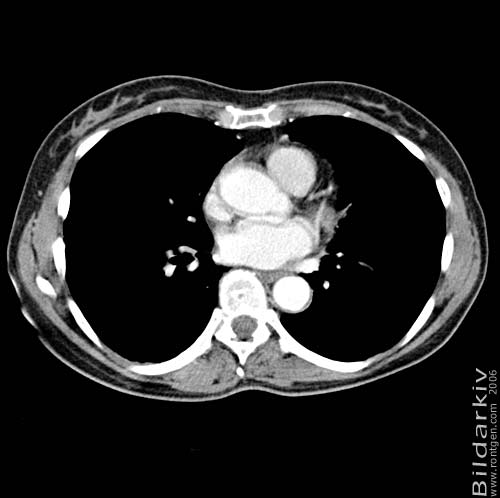

Thorax 34

Snitt över thorax med kontrast. Sk. mediastinum-fönstersättning.

CT Röntgen Helsingborgs lasarett

Mediastinum